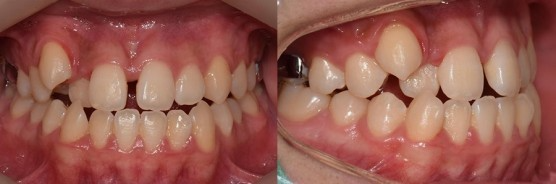

[턱뼈확장장치(구개확장장치)를 이용한 부정교합 치료 케이스]

[상악구개확장장치 시적한 사진]

초진 사진은 아니고, 장치를 시적 한 사진입니다.

양치를 못하는 남자아이입니다.

위턱이 아래턱에 비해 상당히 작은 편입니다.

어금니도 아래가 위를 덮고 있는 양상이며, 앞니도 아랫니가 윗니보다 더 나와있는 상황입니다.